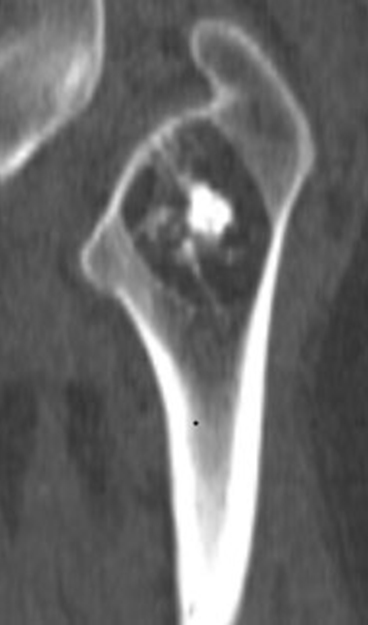

A 42-year-old man presented with a history of progressive left femoral pain radiating to his buttock. He reported worsening symptoms when walking for prolonged periods of time or playing sport. On clinical examination, he had no swelling, no tenderness, nor limitation of movement. Plain radiographs of the left hip showed a lytic lesion containing a central calcification and surrounded by sclerotic margins in the intertrochanteric region of the proximal femur (Figure 1). Axial CT scan reveals intraosseous well defined fat density lesion containing central calcification with sclerotic margins (Figure 2).

Figure 1: Plain radiographs of the left hip showing in intertrochanteric region of the proximal femur with a lytic lesion containing central calcification and surrounded by sclerotic margins.

Intraosseous lipomas usually present as cystic lesions with an increased radiolucency, surrounded by a sclerotic rim (74%) [2]. Lipomas located in the proximal femur may be surrounded by a relatively extensive area of sclerotization [8]. Lesions in the intertrochanteric area of the femur should be differentiated from liposclerosing myxofibrous tumor, a very scarce benign fibro-osseous lesion with mixed histology, which may contain components of lipoma [9].